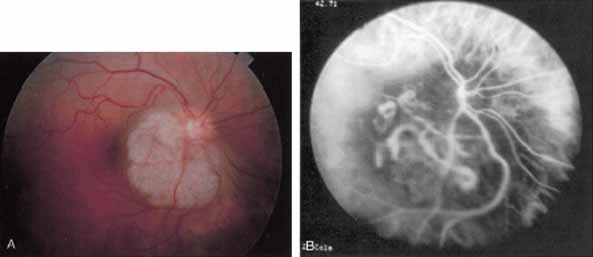

IDIOPATHIC POLYPOIDAL CHOROIDAL VASCULOPATHY

Idiopathic polypoidal choroidal vasculopathy, also known as posterior uveal bleeding syndrome, typically affects darkly pigmented persons who exhibit acute exudative manifestations in the posterior pole, including subretinal hemorrhage and, occasionally, CNV.76,77 ICG angiography facilitates a more definitive diagnosis than fluorescein angiography because it achieves a sharper image of the primary lesion,51,77,78 dilated choroidal vessels terminating in polypoidal or aneurysmal excrescences at the level of the choroid (Fig. 23). These vascular changes account for the secondary exudative and hemorrhagic detachments of the retinal pigment epithelium and neurosensory retina that are characteristic of this disorder. Furthermore, ICG angiography may provide a better means of differentiating the relatively benign aneurysm-like changes at the level of the larger choroidal vessels from CNV, a more devastating secondary manifestation of this chronic disease.79

Fig. 23 A. Clinical photograph of a patient with idiopathic polypoidal choroidal vasculopathy demonstrating the branching lesion at the level of the choroid. There is a more nodular elevation in the inferior macula. A hemorrhagic detachment of the retina is noted temporally in a curvilinear fashion. B. “Green-free” photograph that more vividly demonstrates the branching vascular pattern of this condition. C. High-magnification image of an early-phase indocyanine green (ICG) study reveals filling of the vascular channels at the level of the choroid leading to the polypoidal lesions. Note that the inferior, more elevated lesion, which is nodular on clinical examination, consists of an internal network of branching vessels. D. Late-phase ICG study demonstrates ring-like staining of the small polypoidal lesions. The larger lesion shows intense but nonhomogeneous staining.